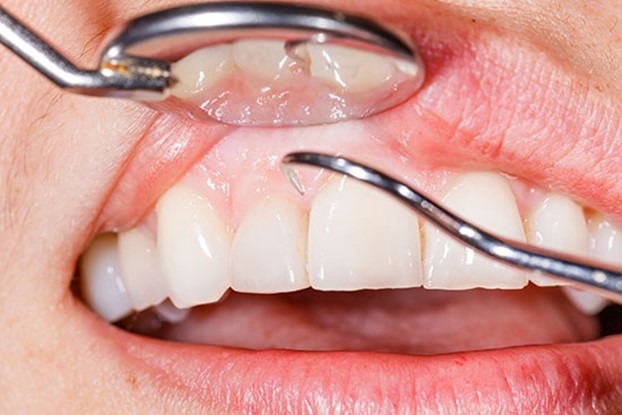

جراحی لثه در انواع مختلف برای پاکسازی لثه و بهبود وضعیت آن انجام میشود. این روشها شامل دیپ اسکیلینگ یا جرمگیری عمیق و روت پلنینگ است و با این روشها، لثه شکافته و از وجود باکتریها پاک شده و سطوح ریشه دندانها صاف میشوند تا فضای اضافی برای رشد باکتریها و تجمع جرم کاهش یابد. بسیاری از دندانپزشکان این دو روش را همزمان انجام میدهند تا بهترین نتیجه را برای بیماران خود به ارمغان بیاورند.